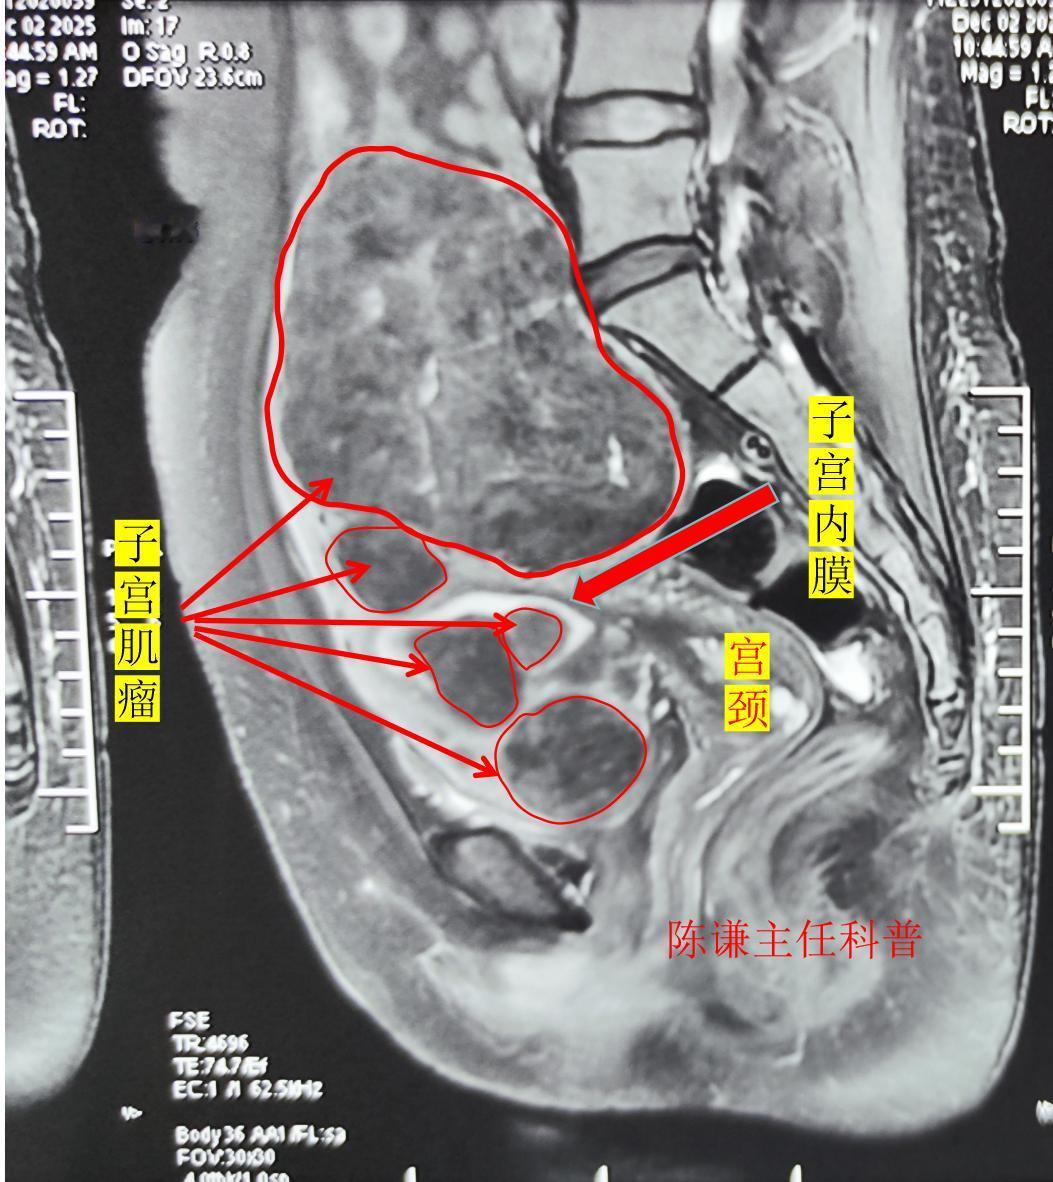

这是我们才治疗的一名多发性子宫肌瘤患者,患者来自上海,发现肌瘤有近10年了,患者的肌瘤涵盖了所有的肌瘤类型,有11厘米大小的浆膜下肌瘤,也有肌壁间肌瘤,还有凸向宫腔的黏膜下肌瘤和带蒂的0型肌瘤。 对于这样的患者,传统的治疗方法一般是手术剔除肌瘤;或者选择微创的宫腹腔镜联合治疗,但是依然存在肌瘤复发的问题,并且手术创伤大,术后恢复慢。 而无创海扶刀治疗是比较适合这种多发性的子宫肌瘤,不仅仅能对浆膜下肌瘤进行消融,还可以同时对肌壁间肌瘤和宫腔内的黏膜下肌瘤进行处理,并且患者术后恢复快,不留疤痕,也不影响日常工作生活。子宫肌瘤 海扶刀